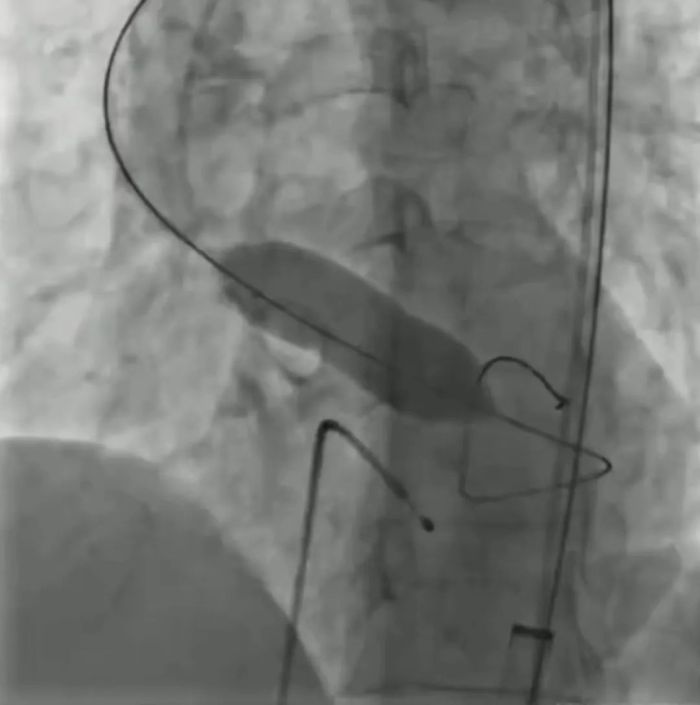

7月24日,六盘水市人民医院心血管内科及相关科室独立成功开展经导管主动脉瓣置换术(TAVR),这也是该团队独立完成的第1例TAVR手术。

7月24日下午,手术团队详细讨论了手术方案及各种风险应对措施,制定详尽的治疗方案和应急预案,由术者唐一锋,助手李勇军、张苡榕及超声、麻醉、护理团队组成手术小组,有条不紊开始手术,从股动脉穿刺——根部造影——跨瓣——球扩——瓣膜过弓——植入瓣膜等系列操作一气呵成,瓣膜植入位置合适,跨瓣压差从51mmHg降至8mmHg,明显改善患者血流动力学,历经3小时,手术圆满成功。术后患者生命体征平稳。